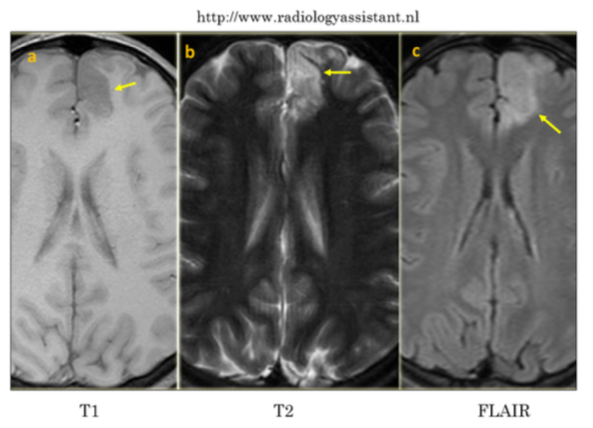

Mostrar la utilidad de la RM en el diagnóstico de patología cerebral en el paciente pediátrico con epilepsia refractaria. Hacer incapié en la necesidad de un protocolo específico con técnicas de alta resolución que aumente la sensibilidad de la RM. Describir los hallazgos más frecuentes causantes de epilepsia en la edad pediátrica.